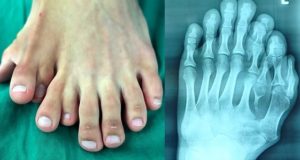

Chinese man born with nine toes undergoes surgery to cut off...